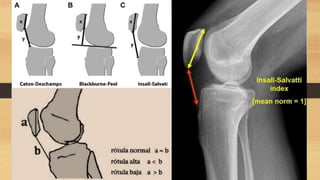

EXAMENES AUXILIARES

Linea de Blumenssat,

cicatriz del cartílago

hialino